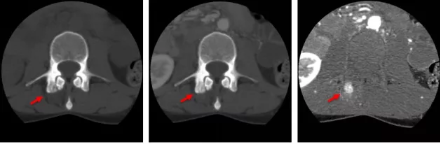

骨智能柔性減影成像功能發(fā)現(xiàn)隱匿骨占位病灶

相比傳統(tǒng)成像方式,肺部柔性減影技術(shù)通過人工智能,對平掃數(shù)據(jù)和CT肺動脈血管掃描數(shù)據(jù)進行智能比對,解碼并識別各個器官(肺、氣管、肺動脈、肺靜脈、主動脈等)的空間位置,并在三維空間中進行體素級的柔性配準(zhǔn),從而極大提升了不同序列數(shù)據(jù)的空間位置的一致性。通過肺部柔性減影技術(shù)可得到肺強化碘圖,可以顯示出傳統(tǒng)CTPA圖像看不到的小栓塞病變,提高了栓塞檢出率,其結(jié)果甚至可與SPECT吻合。

肺智能柔性減影成像功能發(fā)現(xiàn)亞段肺栓塞